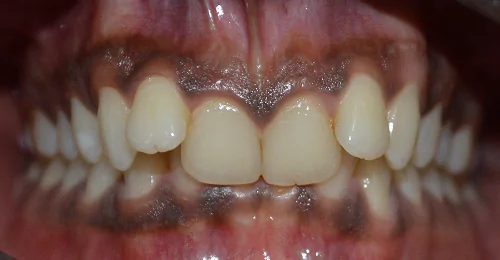

Orthodontic Case – II

(Case Done by Dr. Sonali Deshmukh M.D.S. / Orthodontist )

Correction Of Protruded

Small Lower Jaw

A child with protruded teeth and a small lower jaw at a young age can be treated by Myofunctional appliances which help in the growth of the jaw.

Pre Treatment

After Myofunctional appliances therapy for jaw growth accompanied by braces treatment for correction of protruded teeth.